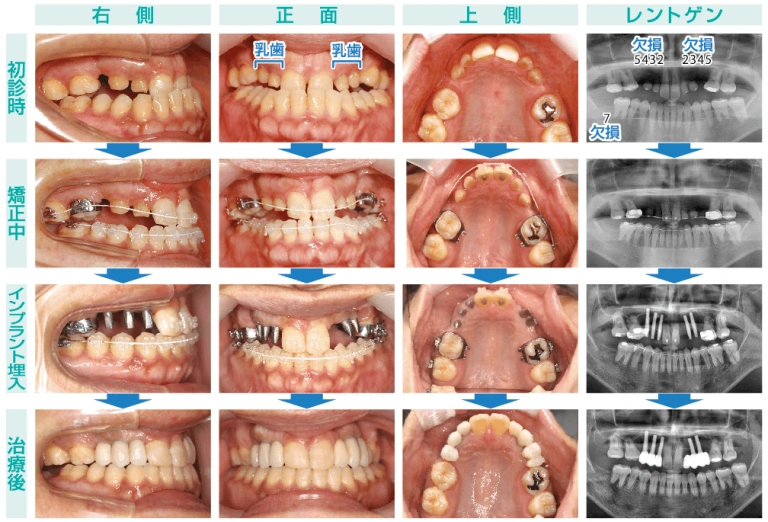

2024/11/24 患者様は40代、女性。先天的に永久歯が9本欠損しており、そこに歯を入れてほしいと来院されました。口腔内を確認すると、上顎に乳歯が4本残存しており、レントゲンにて著しい歯根吸収を認めます。上顎左右2・3・4・5番と右下7番の計9本が欠損しており、治療計画として乳歯抜歯後、上顎左右欠損部にはインプラントを埋入し、前歯部は反対咬合(噛み合わせが逆)になっているため、矯正治療も行うことにしました。

まず、矯正治療にて前歯部の反対咬合を改善する必要があります。骨格性反対咬合の要素が強く、2番から5番にかけて歯がないため、固定源が維持できません。このような矯正治療は非常に難解だと理解していましたが、なんとか被蓋改善を達成し、正常咬合を得ることができました。

しかし、矯正治療後のレントゲン写真にて上下前歯部の歯根吸収がみられました。これは矯正治療のリスクの一つに挙げられショッキングな出来事ですが、矯正治療をすると歯並びがキレイになる反面、その代償としてのリスクがあることもご理解いただけたらと思います。とはいえ、歯根吸収を起こしたからといって歯が抜けるわけではないのでご安心ください。

そして、矯正治療の終盤にインプラントを埋入しました。永久歯がない歯槽骨においては、盛んな骨の改造現象が行われていなかったため、骨幅が非常に薄く、3ミリ径の細いインプラントがギリギリ埋入できるか否かでした。左右とも3本埋入予定とし、右側は3本埋入でき、左側は2本埋入にとどめました。しかし、インプラントの長径は充分確保できたため、安定した初期固定が得られ、予後良好に経過しました。

3ヶ月後、セラミックにて補綴治療をおこない、全ての治療を終了しました。まさに最良の治療法と高品質な材料を使用し、審美性と機能性に優れた歯科治療ができたと感じております。